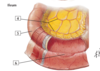

1

1 - superior mesenteric artery

2

2 - middle colic artery

3

3 - straight arteries (arteriae rectae)

4

4 - marginal artery

5

5 - right colic artery

6

6 - ileocolic artery (colic branch, ileal branch)

7

7 - appendicular artery

8

8 - superior rectal artery

9

9 - sigmoid arteries

10

10 - left colic artery

11

11 - inferior mesenteric artery

12

12 - jejnal and ileal (intestinal) arteries